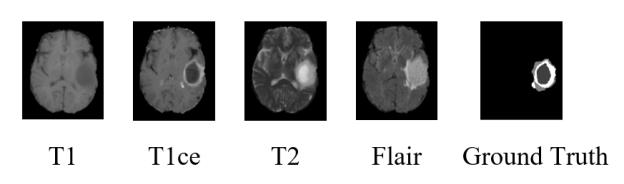

Automatic segmentation of glioma and its subregions is of great significance for diagnosis, treatment and monitoring of disease. In this paper, an augmentation method, called TensorMixup, was proposed and applied to the three dimensional U-Net architecture for brain tumor segmentation. The main ideas included that first, two image patches with size of 128 in three dimensions were selected according to glioma information of ground truth labels from the magnetic resonance imaging data of any two patients with the same modality. Next, a tensor in which all elements were independently sampled from Beta distribution was used to mix the image patches. Then the tensor was mapped to a matrix which was used to mix the one-hot encoded labels of the above image patches. Therefore, a new image and its one-hot encoded label were synthesized. Finally, the new data was used to train the model which could be used to segment glioma. The experimental results show that the mean accuracy of Dice scores are 91.32%, 85.67%, and 82.20% respectively on the whole tumor, tumor core, and enhancing tumor segmentation, which proves that the proposed TensorMixup is feasible and effective for brain tumor segmentation.